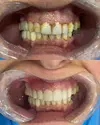

Zirconium applications

Porcelain applications

Laminate veneer